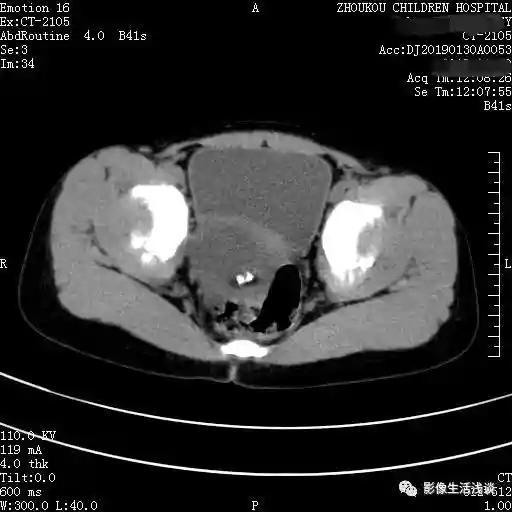

第二个病例女性63岁,体检CT中发现盆腔内左附件区囊性占位:

通过以上病例我们可以发现卵巢畸胎瘤CT表现,大部分情况下是呈多个囊性的病变,囊内套囊。每个囊的信号或者密度是不相同的,各个囊内的内容物也是不相同的。影像学常见的主要是脂肪、液体及骨骼等内容物,有一定的特征性的密度信号。在此情况下就提示是畸胎瘤,部分囊可以见到有头节形成的结节或肿块。如果囊壁的结节比较大呈肿块型,边缘不规则,囊外有侵犯有可能是恶性的。增强扫描囊壁与结节之间可有轻度或中度的强化,根据相应的CT的表现,同时也要结合女性相应的肿瘤标志物、临床表现,来给予综合的判断以及后续的处理,做到早发现早处理,降低恶性畸胎瘤的发病率。